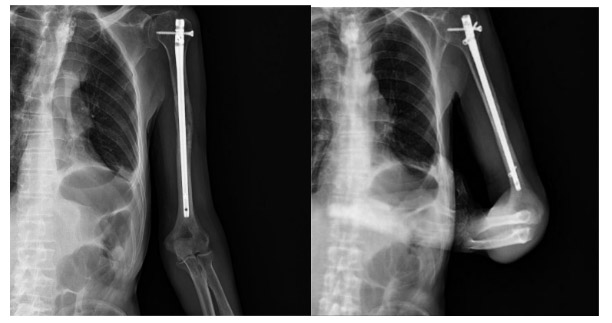

Post-surgery: The X-ray shows an intramedullary nail within the left humerus bone.